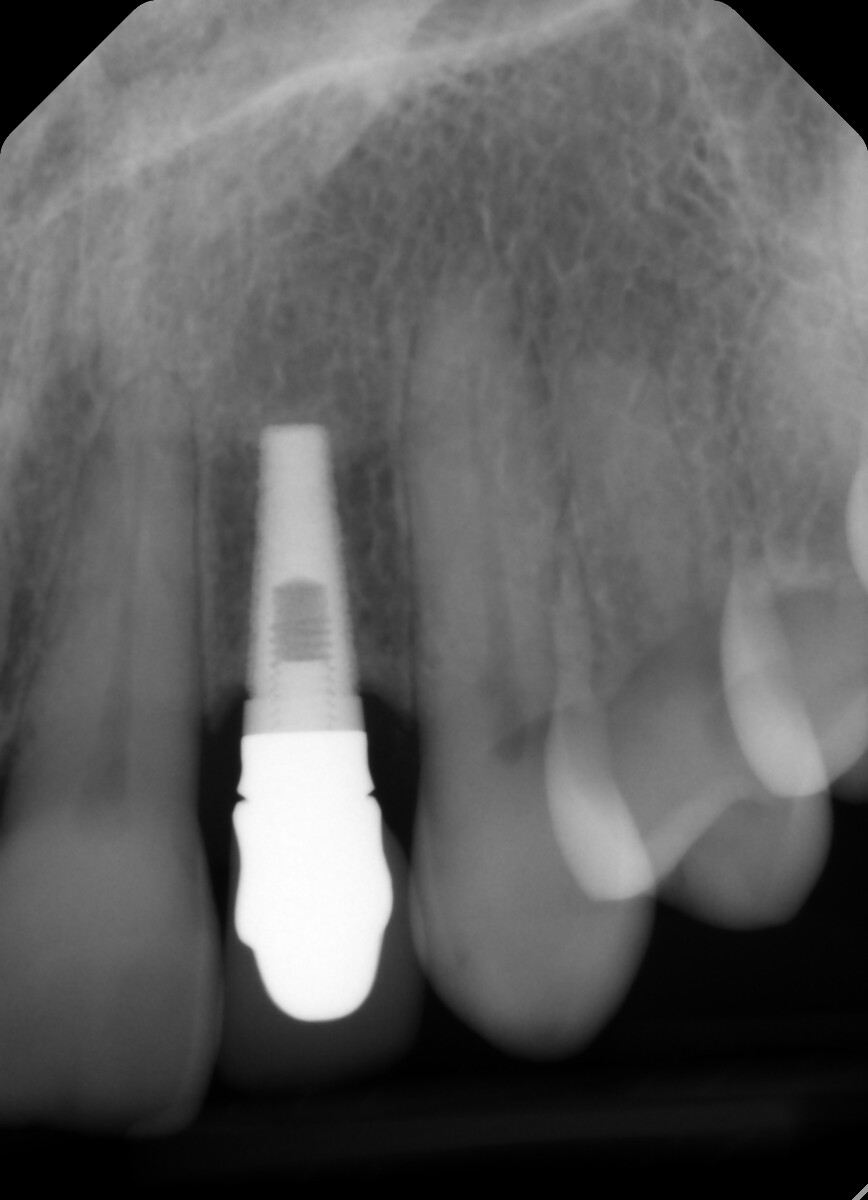

Is there any way you can remove the crown/abutment so we can see the connection. The shape of the fixture looks like it might be an Endopore. Endopore was a beaded fixture from Sybron (Innova) that was popular for a “short” period of time back in the 1990’s and early 2000’s.

This must be an Endopore implant from Innova. It was a Canadian implant that was press fit. It worked well as long as all the beaded surface remained covered in bone.

Yes, this is Innova Endopore external hex. Not sure if it’s 3.5 or 4.1 platform. Guessing 3.5 platform. You can find restorative from Titan Implants. https://titanimplants.com/innova-endopore-entegra-compatible-external-hex/